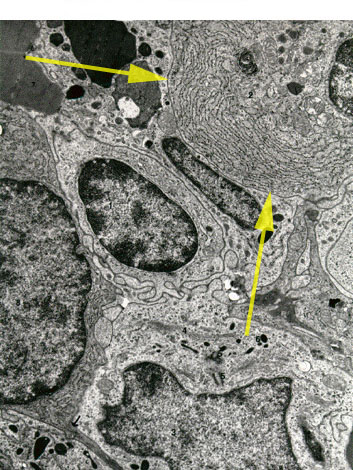

Identify cell.

Answer

Plasma cell